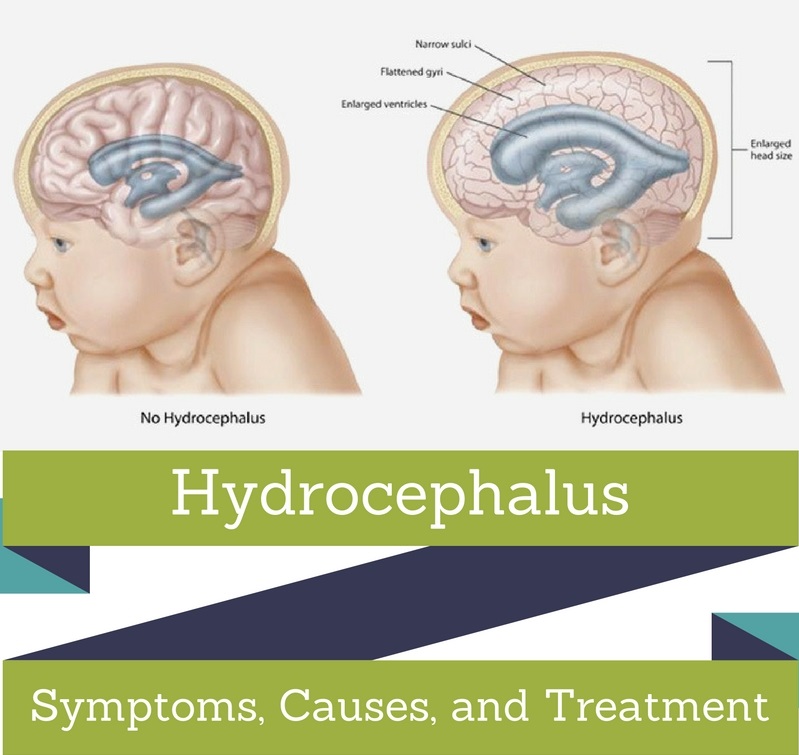

Symptoms And Causes Of Hydrocephalus

Hydrocephalus : Symptoms, Picture, Causes, and Treatment

Hydrocephalus: Causes, Picture, Symptoms And Treatment

Hydrocephalus : Symptoms, Picture, Causes, and Treatment

Hydrocephalus: Symptoms, Causes, Treatment, and Diagnosis | FindATopDoc

Hydrocephalus In Infants – Causes, Symptoms & Treatment | Neonatal …